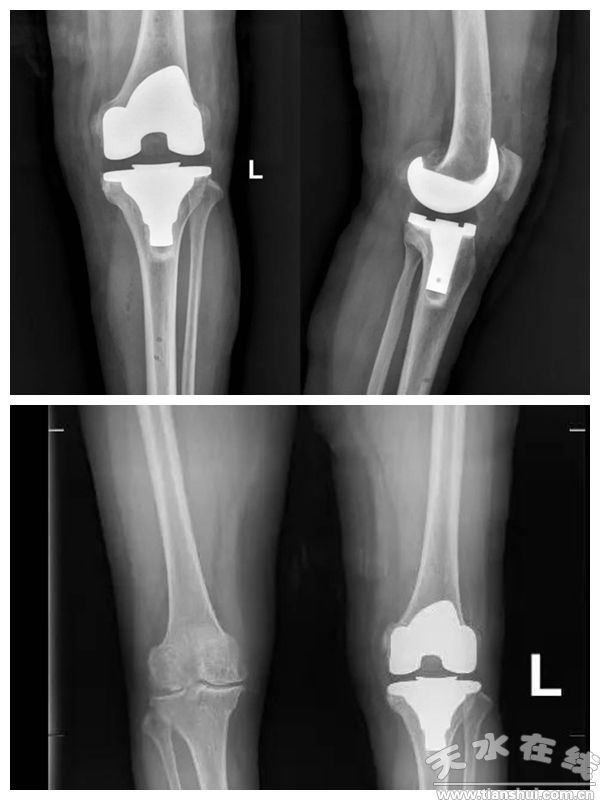

(患者術(shù)后X光線)

機(jī)器人手術(shù)突破了傳統(tǒng)手術(shù)中“手”與“眼”的局限,大幅提升了手術(shù)的精準(zhǔn)性和安全性,有效避免了傳統(tǒng)機(jī)械工具測量誤差及假體位置不佳等問題,為患者術(shù)后快速康復(fù)和遠(yuǎn)期療效提供了堅(jiān)實(shí)保障。